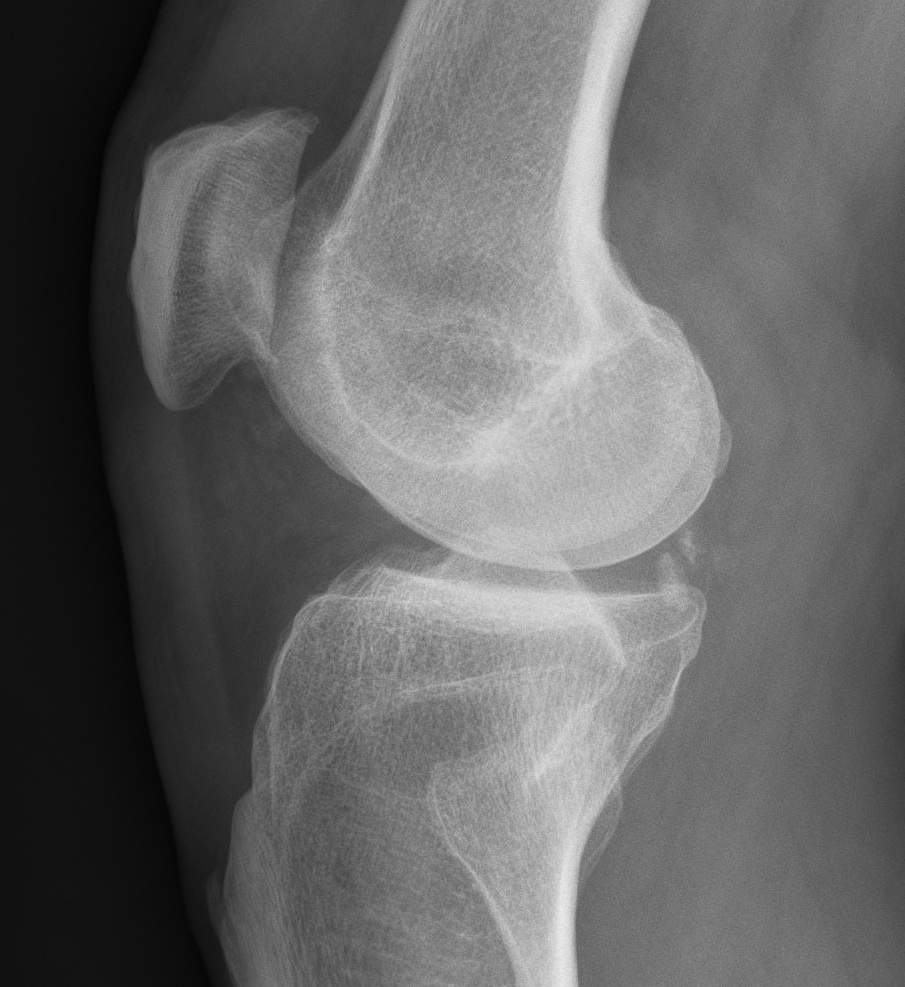

Xray

OA Loose Bodies

OCD Loose Bodies